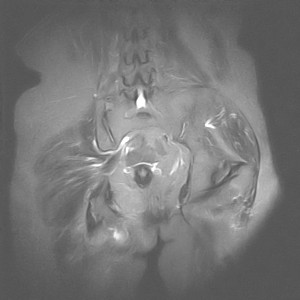

图像太差了 1、右侧臀肌旁脓肿? 建议增强 2、左侧股骨头坏死并半脱位

1、左侧股骨头坏死并髋关节半脱位;

2、右侧臀肌感染,(可能褥疮所致)